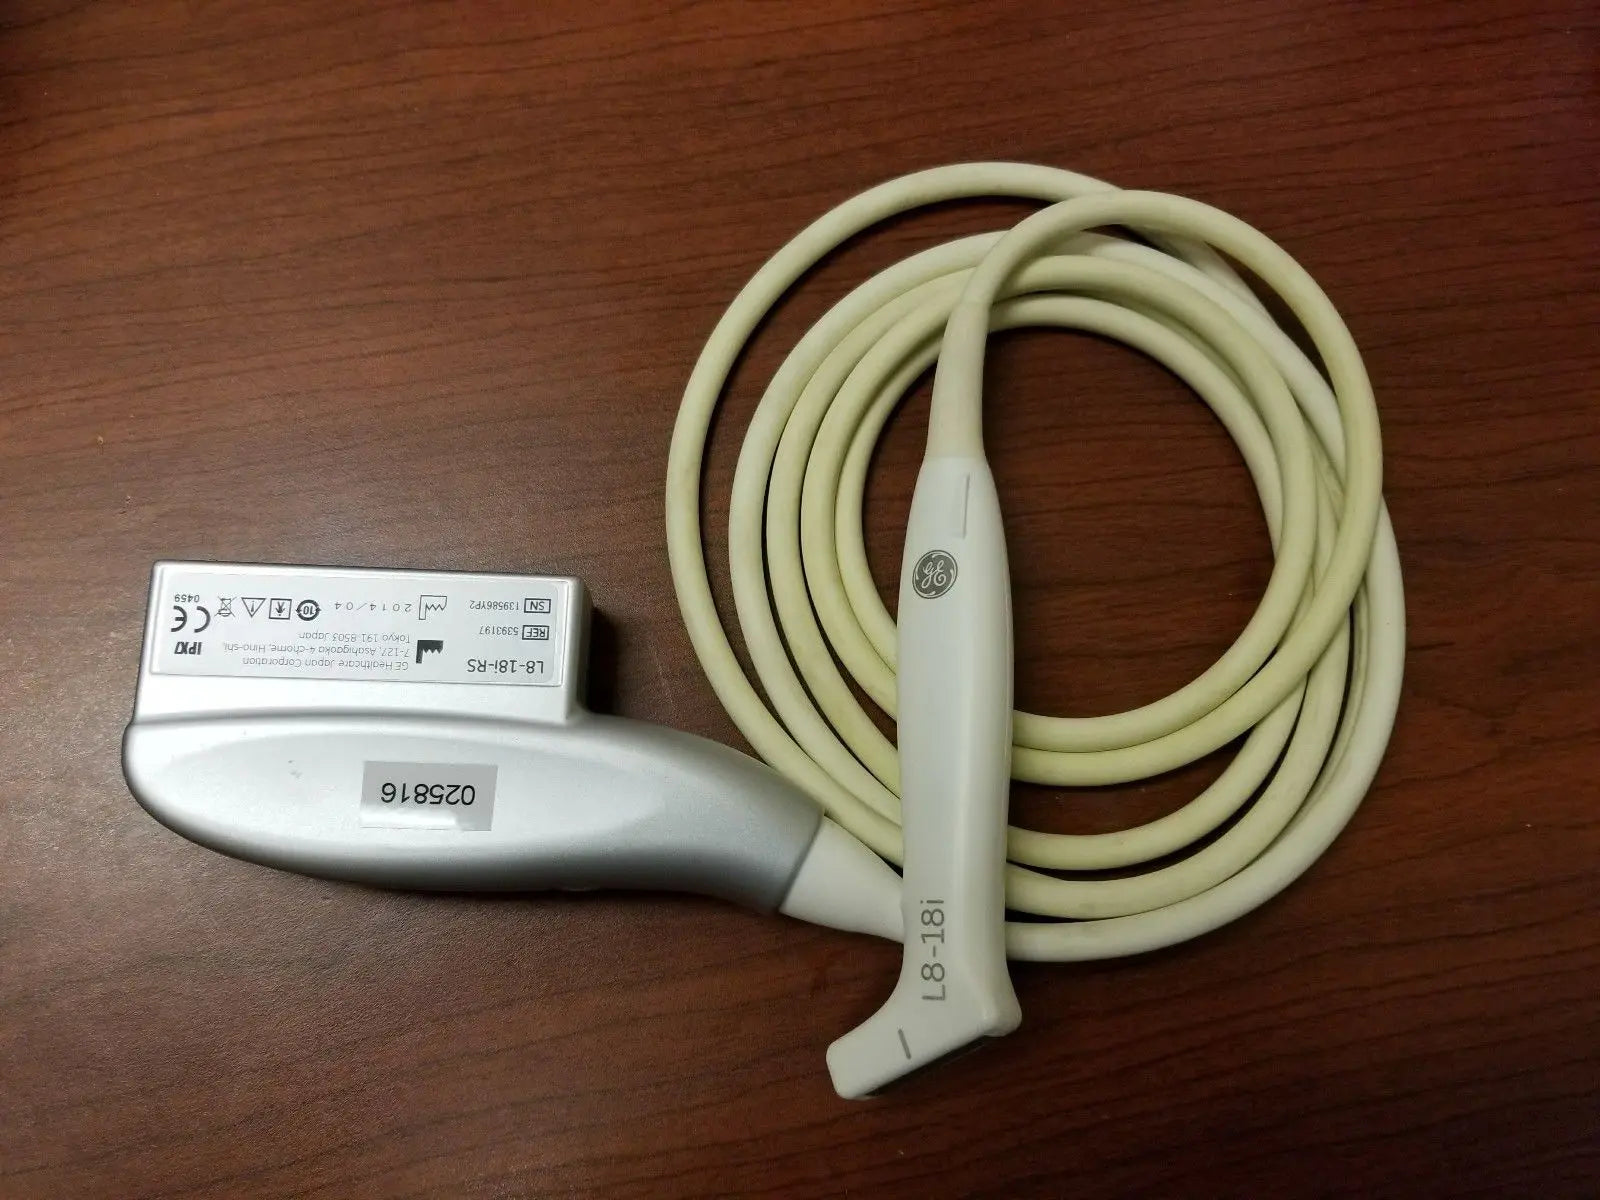

DIAGNOSTIC ULTRASOUND MACHINES FOR SALE

2014 GE L8-18i -RS probe for GE Ultrasound

Sale price$ 7,170.06